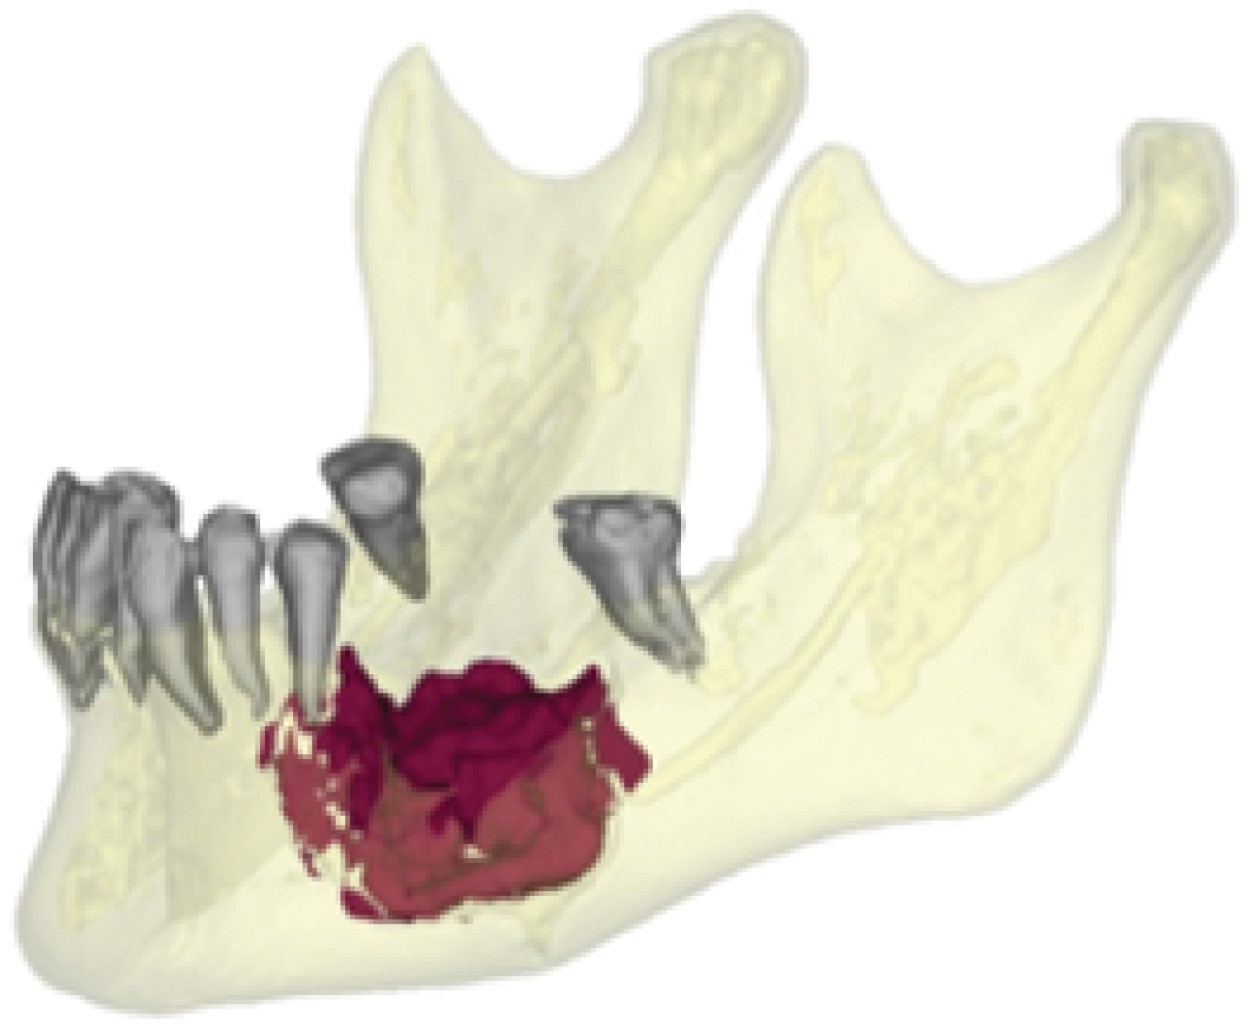

Posterior a un año de controles semanales y sin evidencia de ninguna mejoría posterior a las extracciones y manejo conservador, se decidió en conjunto con paciente y sus familiares manejo quirúrgico con resección mandibular izquierda, para lo que se solicitó TAC, reconstrucción 3D (Figuras 3 y 4), estereolitografía y todos los estudios de laboratorio pertinentes, así como valoración preoperatoria por cardiología, medicina interna y anestesiología, de igual manera el médico oncólogo tratante estuvo enterado y de acuerdo con el tratamiento propuesto.

Figura 3

Figura 4